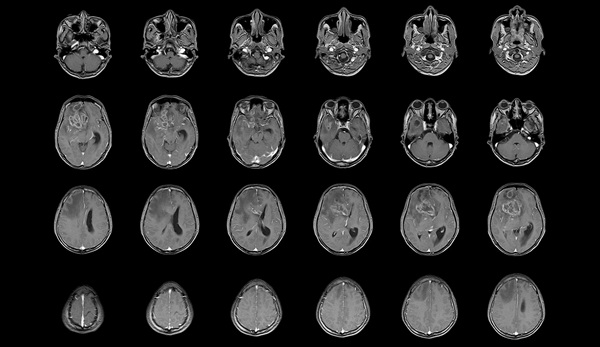

- 3D Scanning Approach Enables Ultra-Precise Brain Surgery